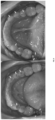

- FIGS. 7 and 8 are illustrations of two patient's dentitions showing different types of wear that would benefit from enamel replacement according to an embodiment of the present disclosure.

- FIG. 7 represents the maxillary arches of two patients. There is clear evidence of wear on the occlusal surfaces of many teeth which appear to have holes, divots, or chips. When topographical examinations of the scanned arches are performed, it is difficult to discern whether the portions requiring replacement are due to missing enamel, composite, or amalgam.

- FIG. 8 represent the same maxillary arches as those in FIG. 7 .

- the left images in FIGS. 7 and 8 are for one patient and the right images are for another.

- the arrows note whether the missing structure is worn enamel, composite, or amalgam. This illuminates the difficulty in discerning whether the excessive structural loss was enamel, dentin, or a dental restorative material when solely viewing the topographical view